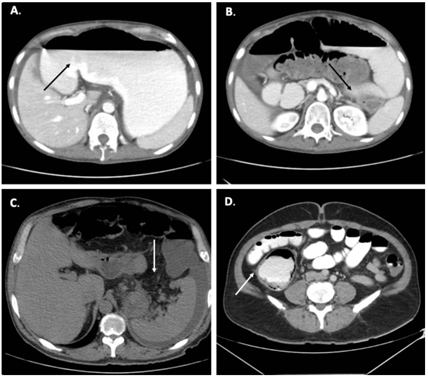

Por eso, es necesario reconocer oportunamente una obstrucción intestinal en asa cerrada y considerarla una urgencia quirúrgica, debido a las consecuencias derivadas de un eventual retraso en su resolución, pues el riesgo de estrangulación e infarto es alto, con tasas de mortalidad del 10 al 35 % 13. La Figura 1 ilustra una representación esquemática y radiológica de una obstrucción intestinal en asa cerrada.

Figura 1. Representación esquemática y radiológica de obstrucción en asa cerrada. A. En la obstrucción en asa cerrada el lumen intestinal es obstruido en dos sitios localizados uno cerca al otro en los puntos de entrada y salida del asa; B. Corte axial de una tomografía de abdomen de un paciente con diagnóstico de vólvulo del sigmoide; C. Radiografía de abdomen de paciente con obstrucción intestinal con relación a vólvulo del sigmoide, se evidencia importante distensión de asas intestinales.